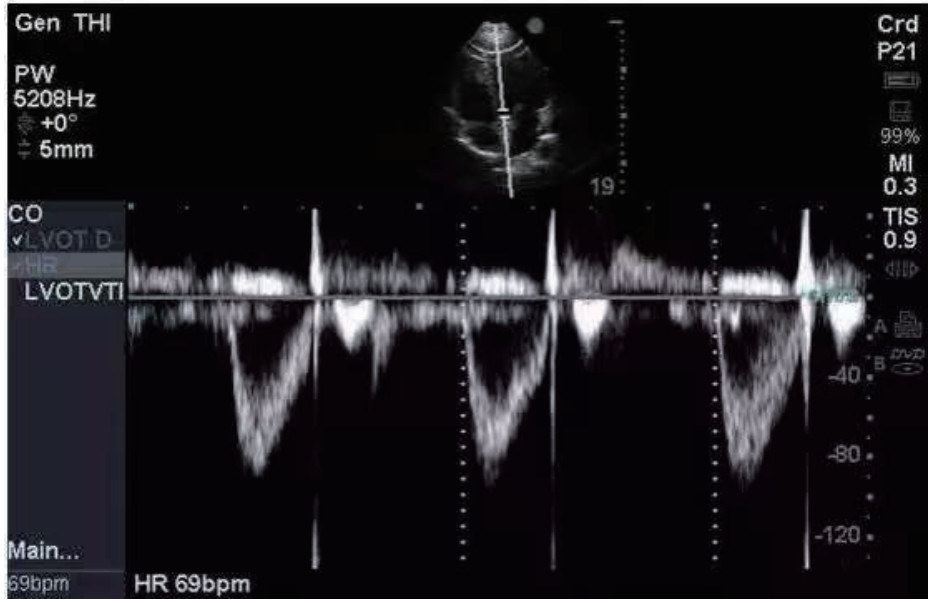

通过查阅电子病历收集CCS患者年龄、性别、是否合并高血压和(或)糖尿病等基础病、急诊入院时头颅CT影像学表现、GCS评分、急性生理学与慢性健康状况评分Ⅱ(APACHE Ⅱ)等基本资料,以及急诊入院后电解质(钾、钠),血液检查指标C反应蛋白(CRP)、葡萄糖(GLU)、肌酸激酶(CK)、肌酸磷酸激酶同工酶(CKMB)、乳酸脱氢酶(LDH)、神经元特异度烯醇化酶(NSE),手术后转入ICU监测床边心脏彩超指标:速度时间积分(VTI)(见图 1)、射血分数(EF),右心Tei指数,术后颅内压(ICP)及相应时间的视神经鞘直径(ONSD),记录术后第3天ICP,并计算ICP变化率=(术后ICP-术后第3天ICP)/术后ICP等临床资料,记录两组患者转入ICU是否使用血管活性药物及用量(重酒石酸去甲肾上腺素注射液生产厂家:远大医药(中国)有限公司,批准文号:国药准字H42021301,规格:2 mg/支),镇静镇痛等治疗用量及平均每日液体平衡量等指标,其中镇痛药物使用注射用盐酸瑞芬太尼(生产厂家:宜昌人福药业有限责任,批准文号:国药准字H20030197,规格:1 mg/瓶),镇静药物为丙泊酚注射液(生产厂家:西安力邦制药有限公司,批准文号:国药准字H19990282,规格0.2 g/支)。心脏彩超及ONSD测量均为本院通过重症超声规范化培训并取得合格证书者完成,心脏彩超测量采用EDGE型彩色多普勒超声仪(美国索诺声公司)检测,其中Tei指数是由多普勒超声衍生而出的时间间期指数,定义为等容收缩时间(ICT)与等容舒张时间(IRT)之和除以射血时间(ET)。Tei指数的计算公式:Tei指数=(ICT+IRT)/ET。连续测量3次取平均数。ONSD采用EDGE型彩色多普勒超声仪(美国索诺声公司)高频(5.0~10.5 MHz)线阵超声探头测量眼球后3 mm位置视神经鞘的宽度,并反复测量3次取平均值(见图 2)。

图 1 VTI测量 Fig 1 VTI measurement